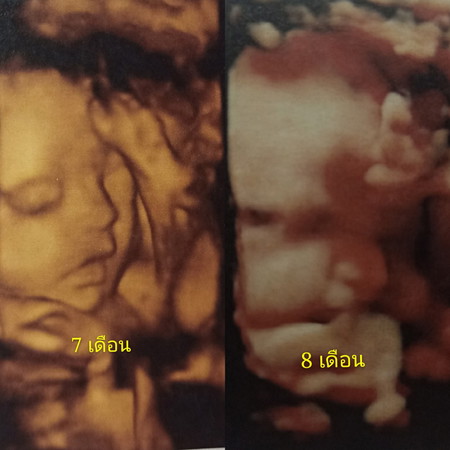

แก้มป่องขึ้น

31 week 3 day อยากเจอหน้าไวๆแล้ว

ใกล้แล้ววค่ะแม่ น้องโตเต็มที่แล้วว แก้มมามากเลยจร้าออกมา จ้ำม่ำน่าดู 🥰😍

แก้มเยอะขึ้นจริงๆด้วย แข็งแรงทั้งคู่นะคะ